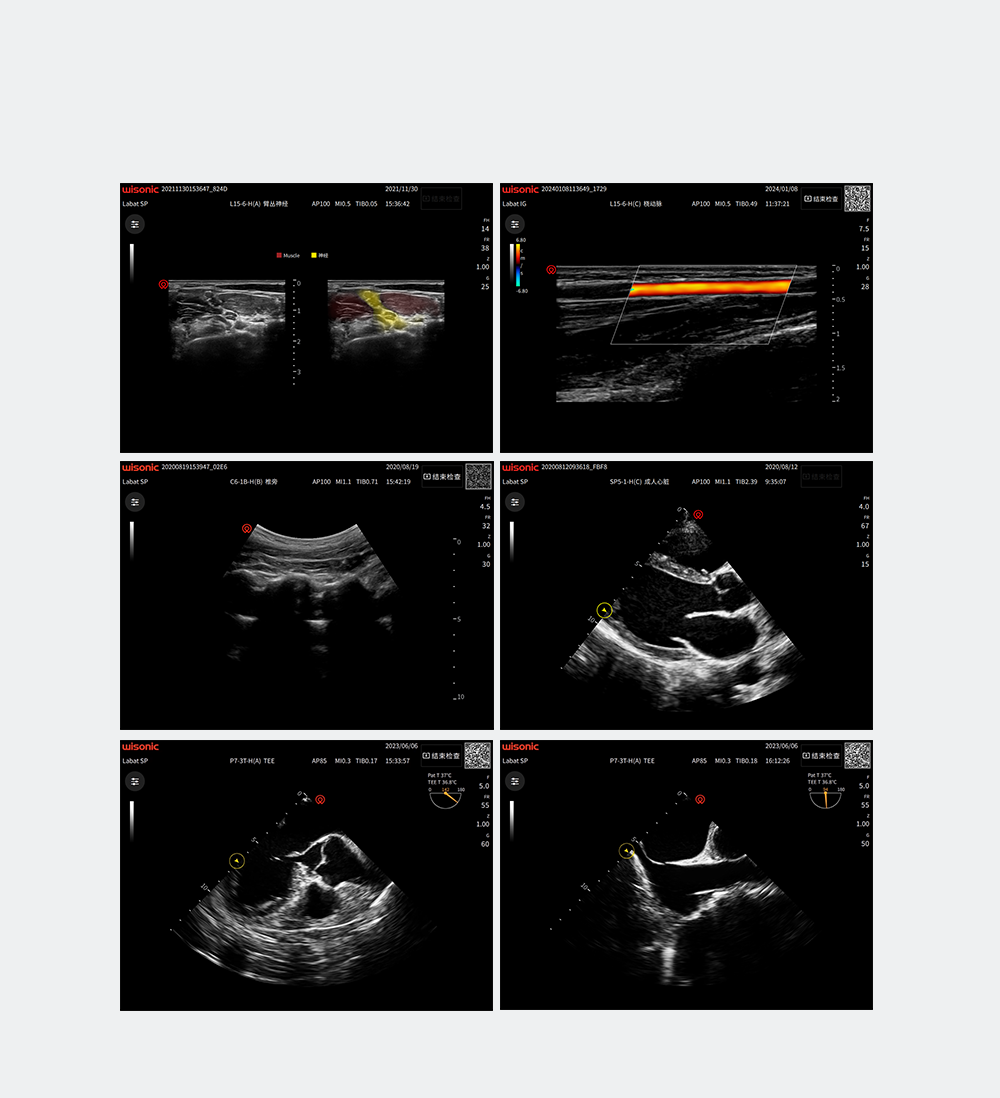

wiNerve

Интеллектуальное распознавание нервов с помощью искусственного интеллекта

Распознавание в реальном времени

Облачное решение

Поддержка нескольких нервов

Application pictures